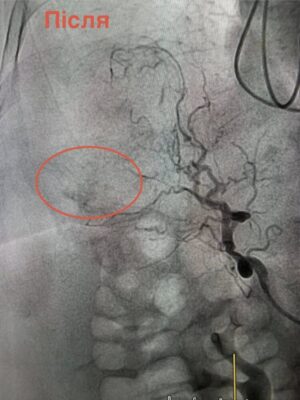

Через загрозливий стан проводити відкриту операцію було неможливо. Натомість лікарі застосували метод ендоваскулярної хірургії — за допомогою ангіографії визначили джерело кровотечі та виконали емболізацію судини, що дозволило її зупинити без масштабного хірургічного втручання.